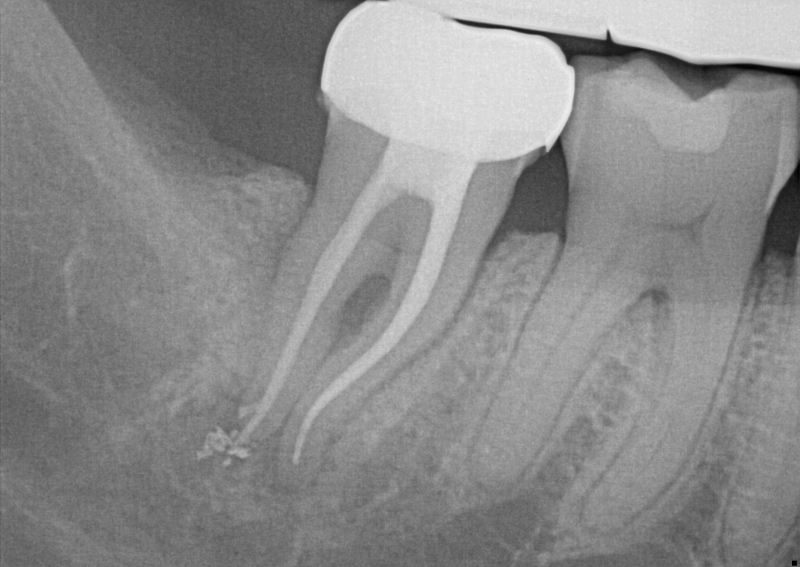

Tooth decay happens when starches and sugar feed on the teeth, attacking this. If you don’t handle this, it leads to fillings, crowns, extractions, and root canals, which are expensive and not fun.